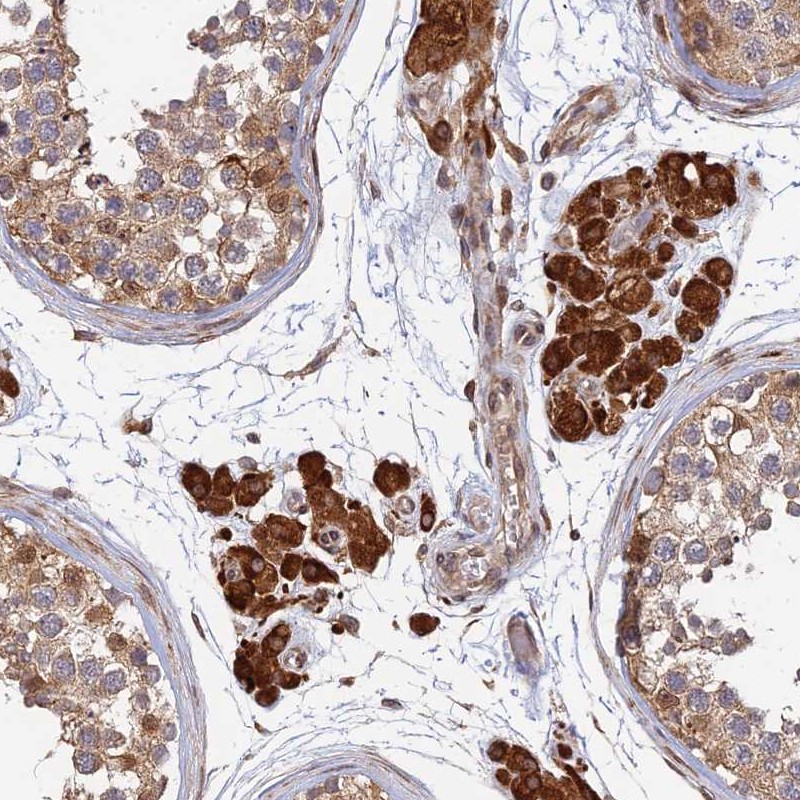

Immunohistochemical staining of human testis shows strong cytoplasmic positivity in leydig cells.